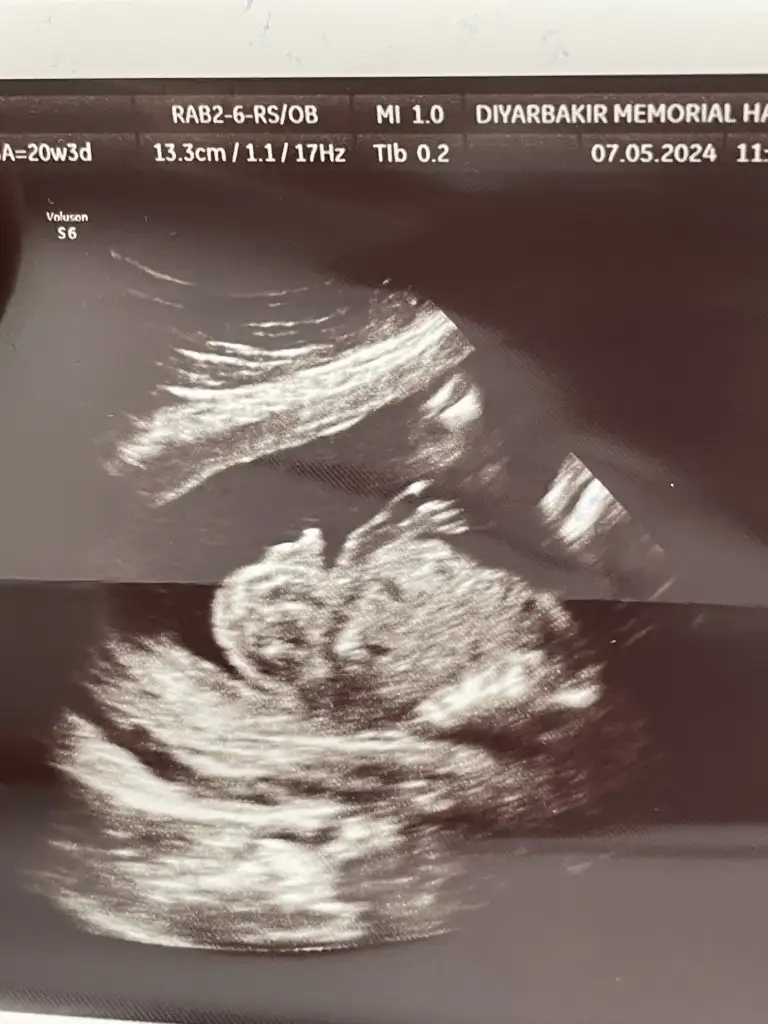

Kızlar bizede 20.haftaya kadar net kız dendi yavrumun genital organını gösterdiler en son bu hafta baktı pipi gibi çıkıntı gördü 3 doktora gittik hepsi belirsiz dedi ambigus genitalya tanısı dediler yıkıldık hemen amniyosemtez yaptık bekliyorum bu da en son ultrason resimleri